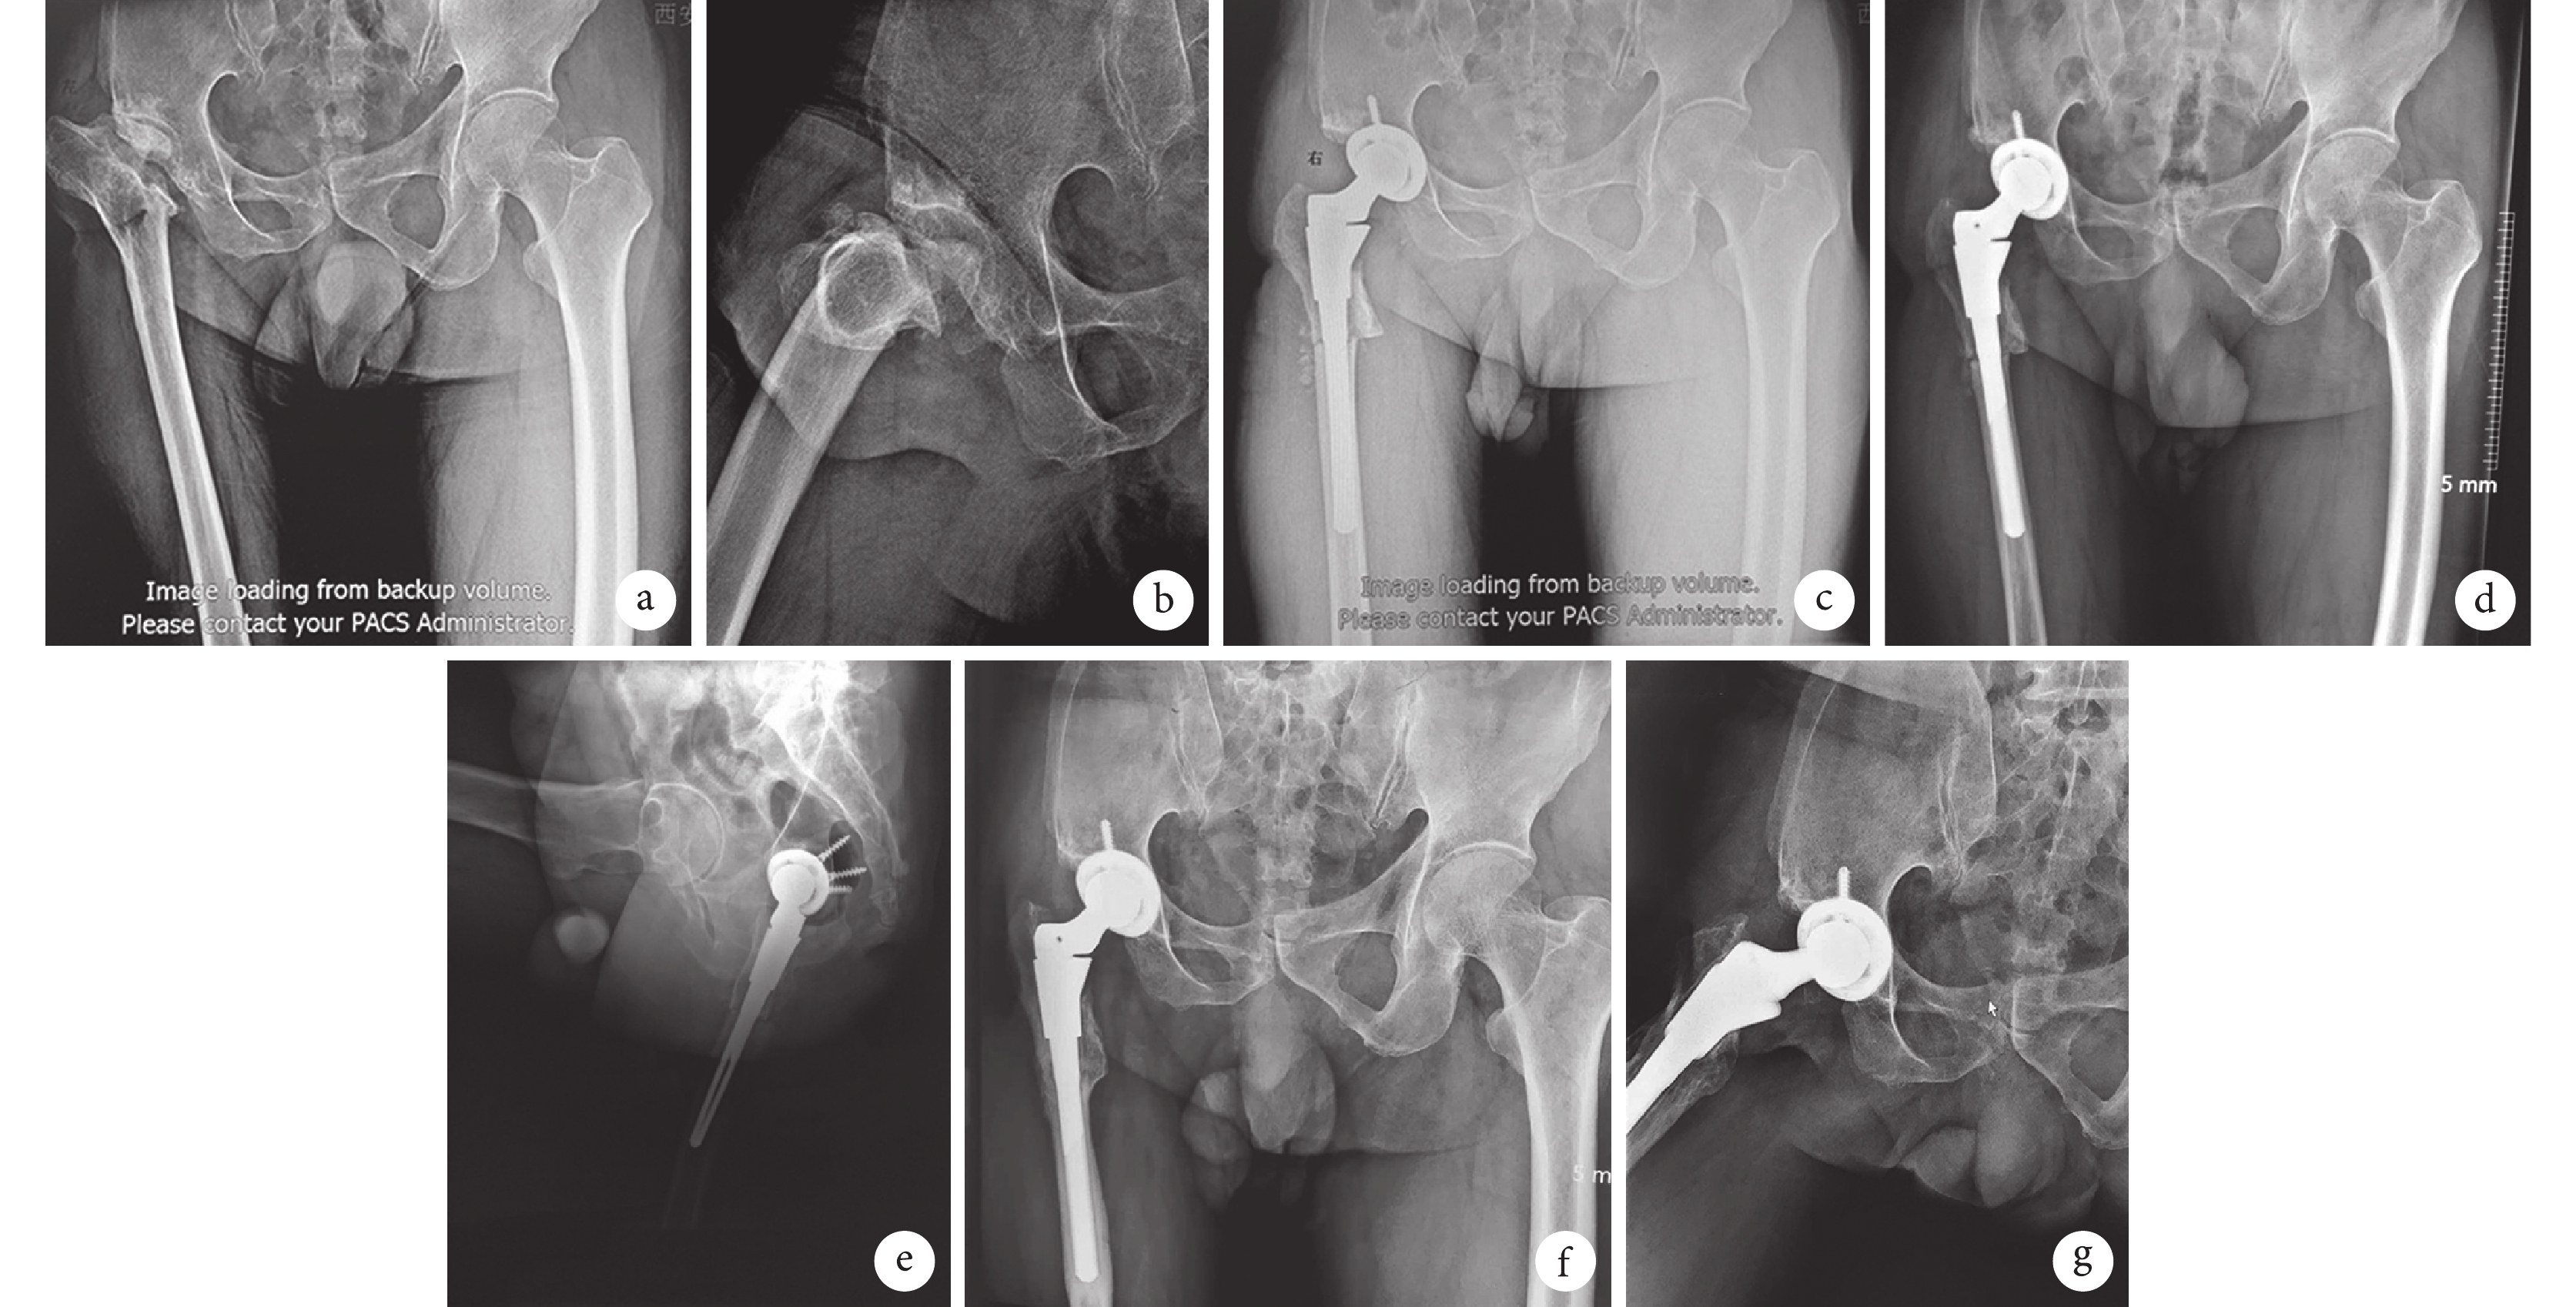

依據 Gao 等[10]提出的活動性感染診斷標準,術中留取組織細菌培養結果均為陰性。術后切口均Ⅰ期愈合。術后 1 例出現坐骨神經刺激癥狀,使用營養神經藥物 3 個月后癥狀消失;1 例采用陶瓷對陶瓷人工關節置換者術后 2 周半臥位時發生關節后脫位,給予閉合復位并持續皮膚牽引 1 周后,未再出現脫位。患者均獲隨訪,隨訪時間 10~63 個月,平均 34 個月。末次隨訪時,患者髖關節局部無紅腫,無皮溫增高;白細胞計數為(5.72±0.57)×109/L,C 反應蛋白為(0.25±0.05)mg/L,降鈣素原為(0.31 ±0.87) ng/mL,紅細胞沉降率為(36.35±9.49)mm/1 h;其中,紅細胞沉降率較術前升高并高于正常值范圍,考慮為生理性原因;白細胞計數、降鈣素原以及 C 反應蛋白均在正常范圍內。術后患者關節功能均逐漸恢復。其中,Harris 評分總分、關節功能評分手術前后各時間點比較,差異均有統計學意義(P<0.05)。疼痛評分術后各時間點與術前比較,差異有統計學意義(P<0.05);術后除 3、6 個月比較差異無統計學意義(P>0.05)外,其余兩兩比較差異有統計學意義(P<0.05)。活動度評分除術后 3 個月與術前比較差異無統計學意義(P>0.05)外,其余各時間點間比較差異均有統計學意義(P<0.05)。畸形評分手術前后比較,差異均無統計學意義(P>0.05)。見表 1。髖關節功能獲優 8 例、良 19 例、中 4 例,優良率達 87%。隨訪期間均無感染再發。X 線片復查示無斑片狀骨密度降低及點狀硬化,無透亮區。與健側相比,患側肢體無過長,其中 5 例未完全達到等長,短縮長度為 0.4~1.3 cm,平均 0.6 cm;但患者均無明顯跛行,無肢體不等長主觀感覺。見圖 1。

a、b. 術前正側位 X 線片;c. 術后即刻正位 X 線片;d、e. 術后 3 個月正側位 X 線片;f、g. 術后 30 個月正側位 X 線片

Figure1. A 50-year-old male patient after operation of the right hip caused by pyogenic arthritis in childhood was treated with THA because of hip pain and deformitya, b. Anteroposterior and lateral X-ray films before operation; c. Anteroposterior X-ray film at immediate after operation; d, e. Anteroposterior and lateral X-ray films at 3 months after operation; f, g. Anteroposterior and lateral X-films at 30 months after operation